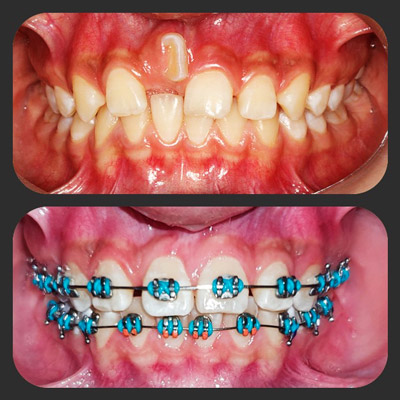

img

La paciente se sentía inconforme con su sonrisa, después del tratamiento mejoró su autoestima y seguridad en su persona y su forma de sonreír.